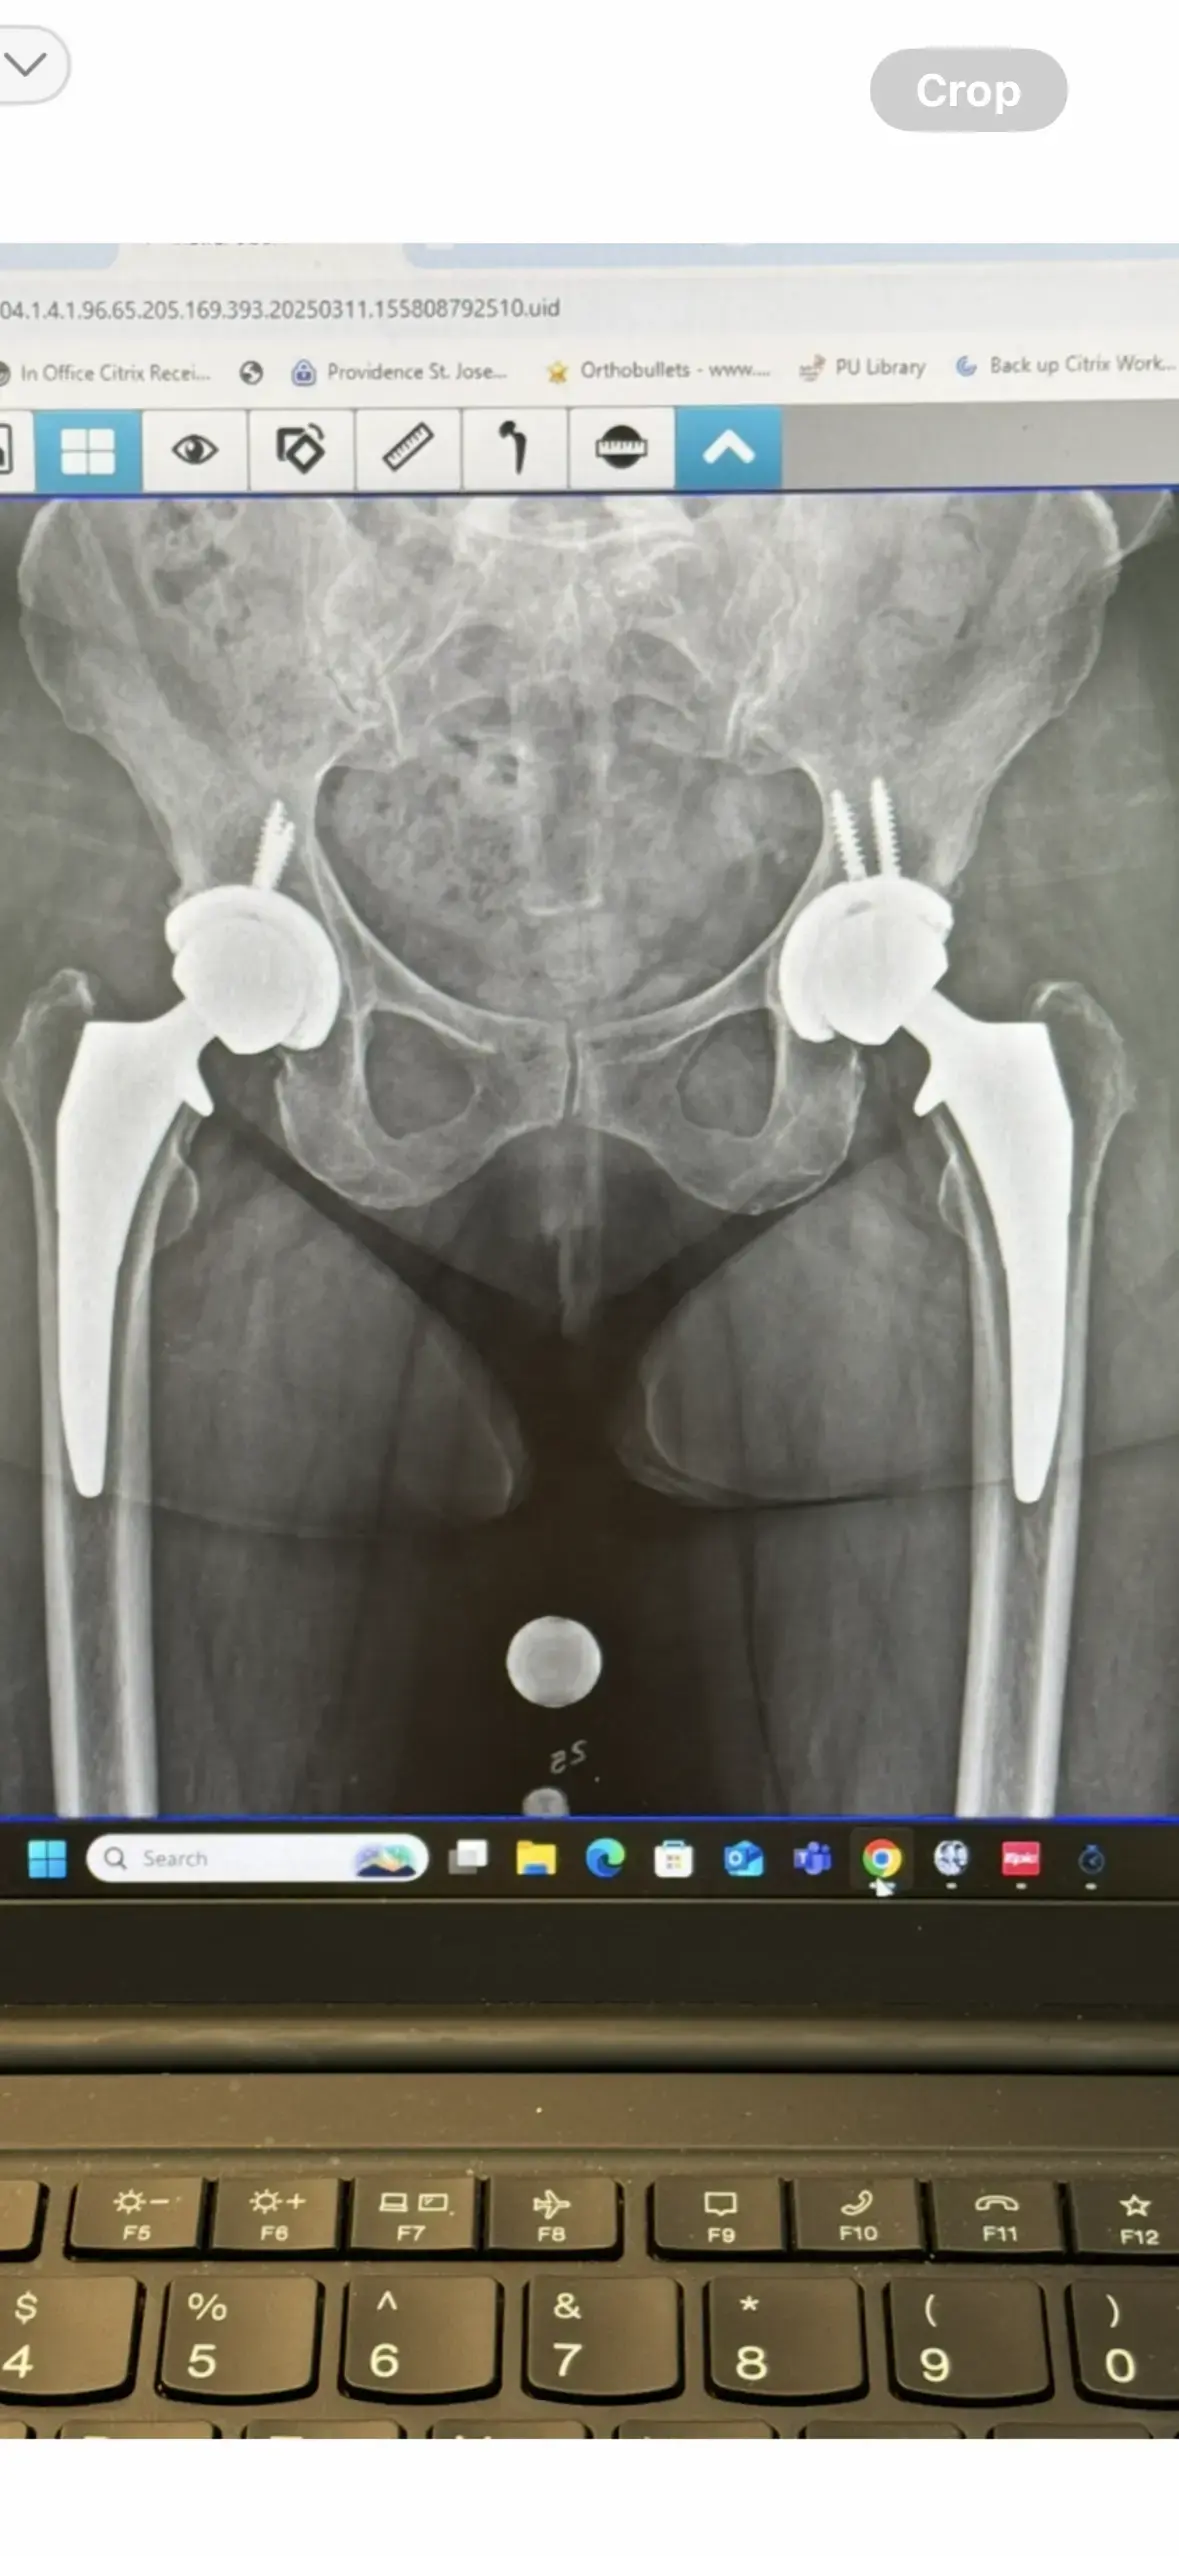

Located in Portland, Oregon, Orthopedic + Fracture Specialists is a dedicated orthopedic center that has been serving the community for over 90 years. Our practice focuses on comprehensive musculoskeletal care, offering everything from pediatric orthopedics to advanced joint replacement surgery, and we are committed to putting your life back in motion. Our multidisciplinary team combines cutting‑edge regenerative medicine—such as platelet‑rich plasma (PRP) injections and stem cell therapy—with proven non‑surgical treatments like physical therapy, sports medicine, and interventional pain management. Whether you need a minimally invasive in‑office procedure, a total hip or knee replacement, or a personalized rehabilitation program, we tailor each plan to your specific condition and goals. The expertise of our board‑certified orthopedic surgeons, physician associates, physical therapists, and hand therapists, coupled with our long‑standing community involvement, ensures that every patient receives the highest standard of care.